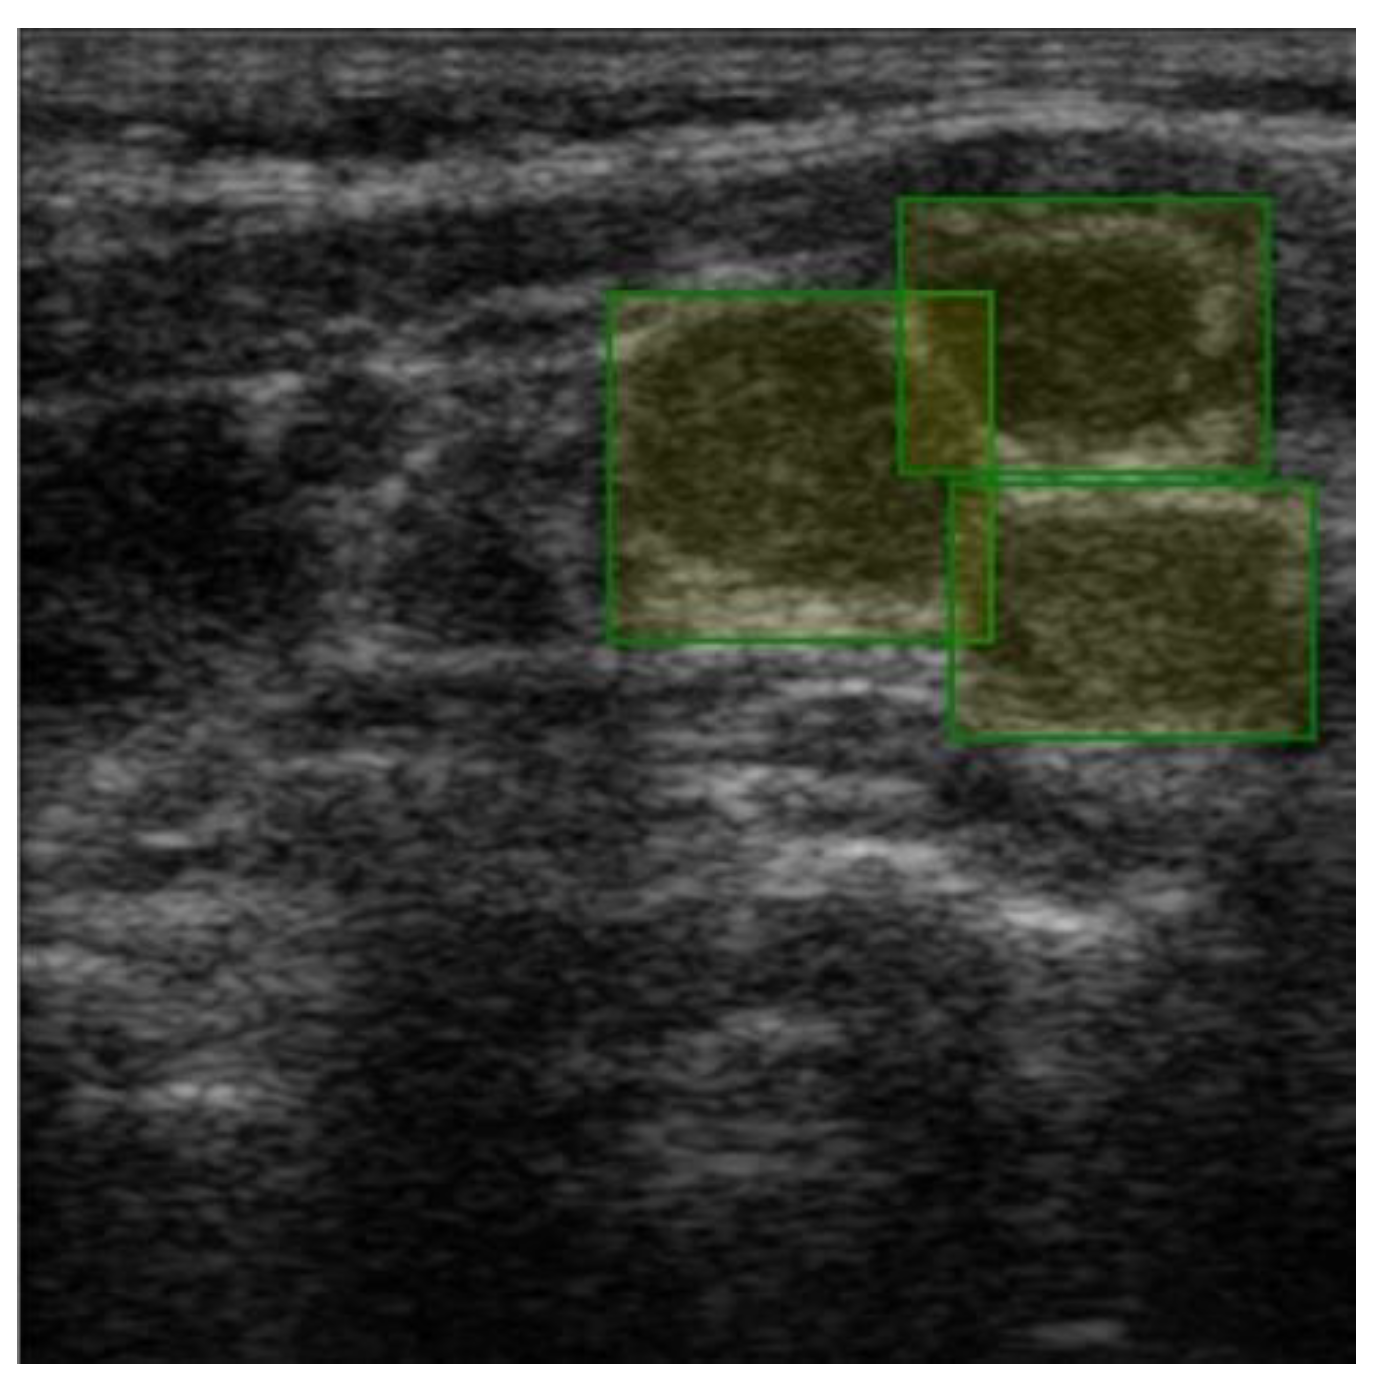

The images were exported from the device used in .jpg format (Figure 1) directly from the US machine and processed by cropping them and resizing them to 469 × 469 pixels (Figure 2).

Labeling was conducted using a free online tool (ImgLab) (Figure 3). The labels were made by the team of physicians that selected the images. Overlapping labels were not a problem for our neural network because the lymph nodes were individually cropped. Therefore, the lymph node images within an adenopathic block were all labeled individually (Figure 4). The labels were saved in .json file format.

Figure 3. Manually created label over a single malignant adenopathy, generating X and Y coordinates for each corner of the box.

Figure 4. Individual labels on each lymph node, generating X and Y coordinates for each corner of each box.